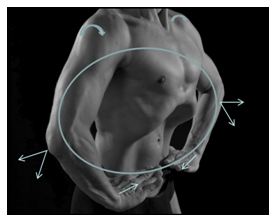

En el terreno práctico, cada postura articular incluida en los ejercicios de TH

ha sido estudiada para responder a las pautas de ejecución anteriormente

descritas. Sirve de ejemplo la rotación interna de los hombros, en flexión de

codos a 90º y flexión dorsal de las muñecas, al máximo de las posibilidades

articulares como se muestra en la figura 2. La repetición diaria de los

ejercicios, crea a largo plazo redes neuronales reverberantes es decir,

circuitos autoexcitadores en situación postural. Dicha estimulación postural y

respiratoria conducen a una tonificación por vía refleja del suelo pélvico

(aumento del 58 % del tono de reposo) y de la faja abdominal (Caufriez,

Fernández, Deman y Wary-Thys, 2007).

Figura

4. Colocación de los miembros superiores en una TH (Caufriez et al. 2010)